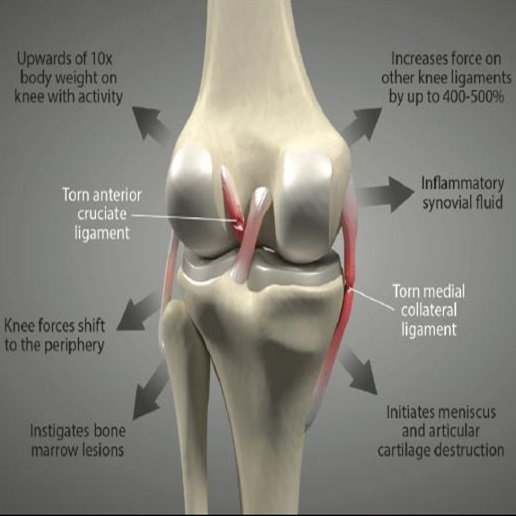

Ligament Injuries

Effective treatment and rehabilitation for ligament tears and associated injuries.

Ligament Injuries